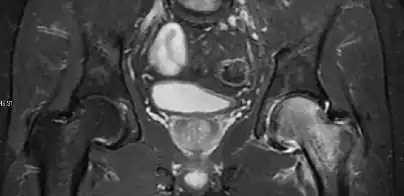

Radiological signs of transient osteoporosis of the hip include localized osteoporosis of the femoral head and neck (Figure 8). Nevertheless, final diagnosis has to be made with MRI to differentiate it from avascular necrosis and from insufficiency or stress fractures of the femoral head or neck. In case of AVN, radiographs can only demonstrate delayed or advanced signs. Staging according to Ficat classification ranges between normal appearance (stage I), slight increased density in the femoral head (stage II), subchondral collapse of the femoral head with or without “crescent” sign (stage III), and advanced collapse with secondary osteoarthritis (stage IV). In the case of stress or insufficiency fractures X-ray sensitivity has been proven to be much lower than MRI, which is currently the gold standard.[1]

Figure 8:

-

X-ray of a patient with transient osteoporosis of the left hip showing osteoporosis.[1] -

Coronal stir imaging in transient osteoporosis, showing diffuse edema.[1] -

Scintigraphy (A), sagittal T1 (B), and coronal PD fat sat of a patient with a subchondral fracture of the femoral head with convex shape to the articular surface.[1] -

Coronal T1 of a patient with avascular necrosis of the femoral head.[1]